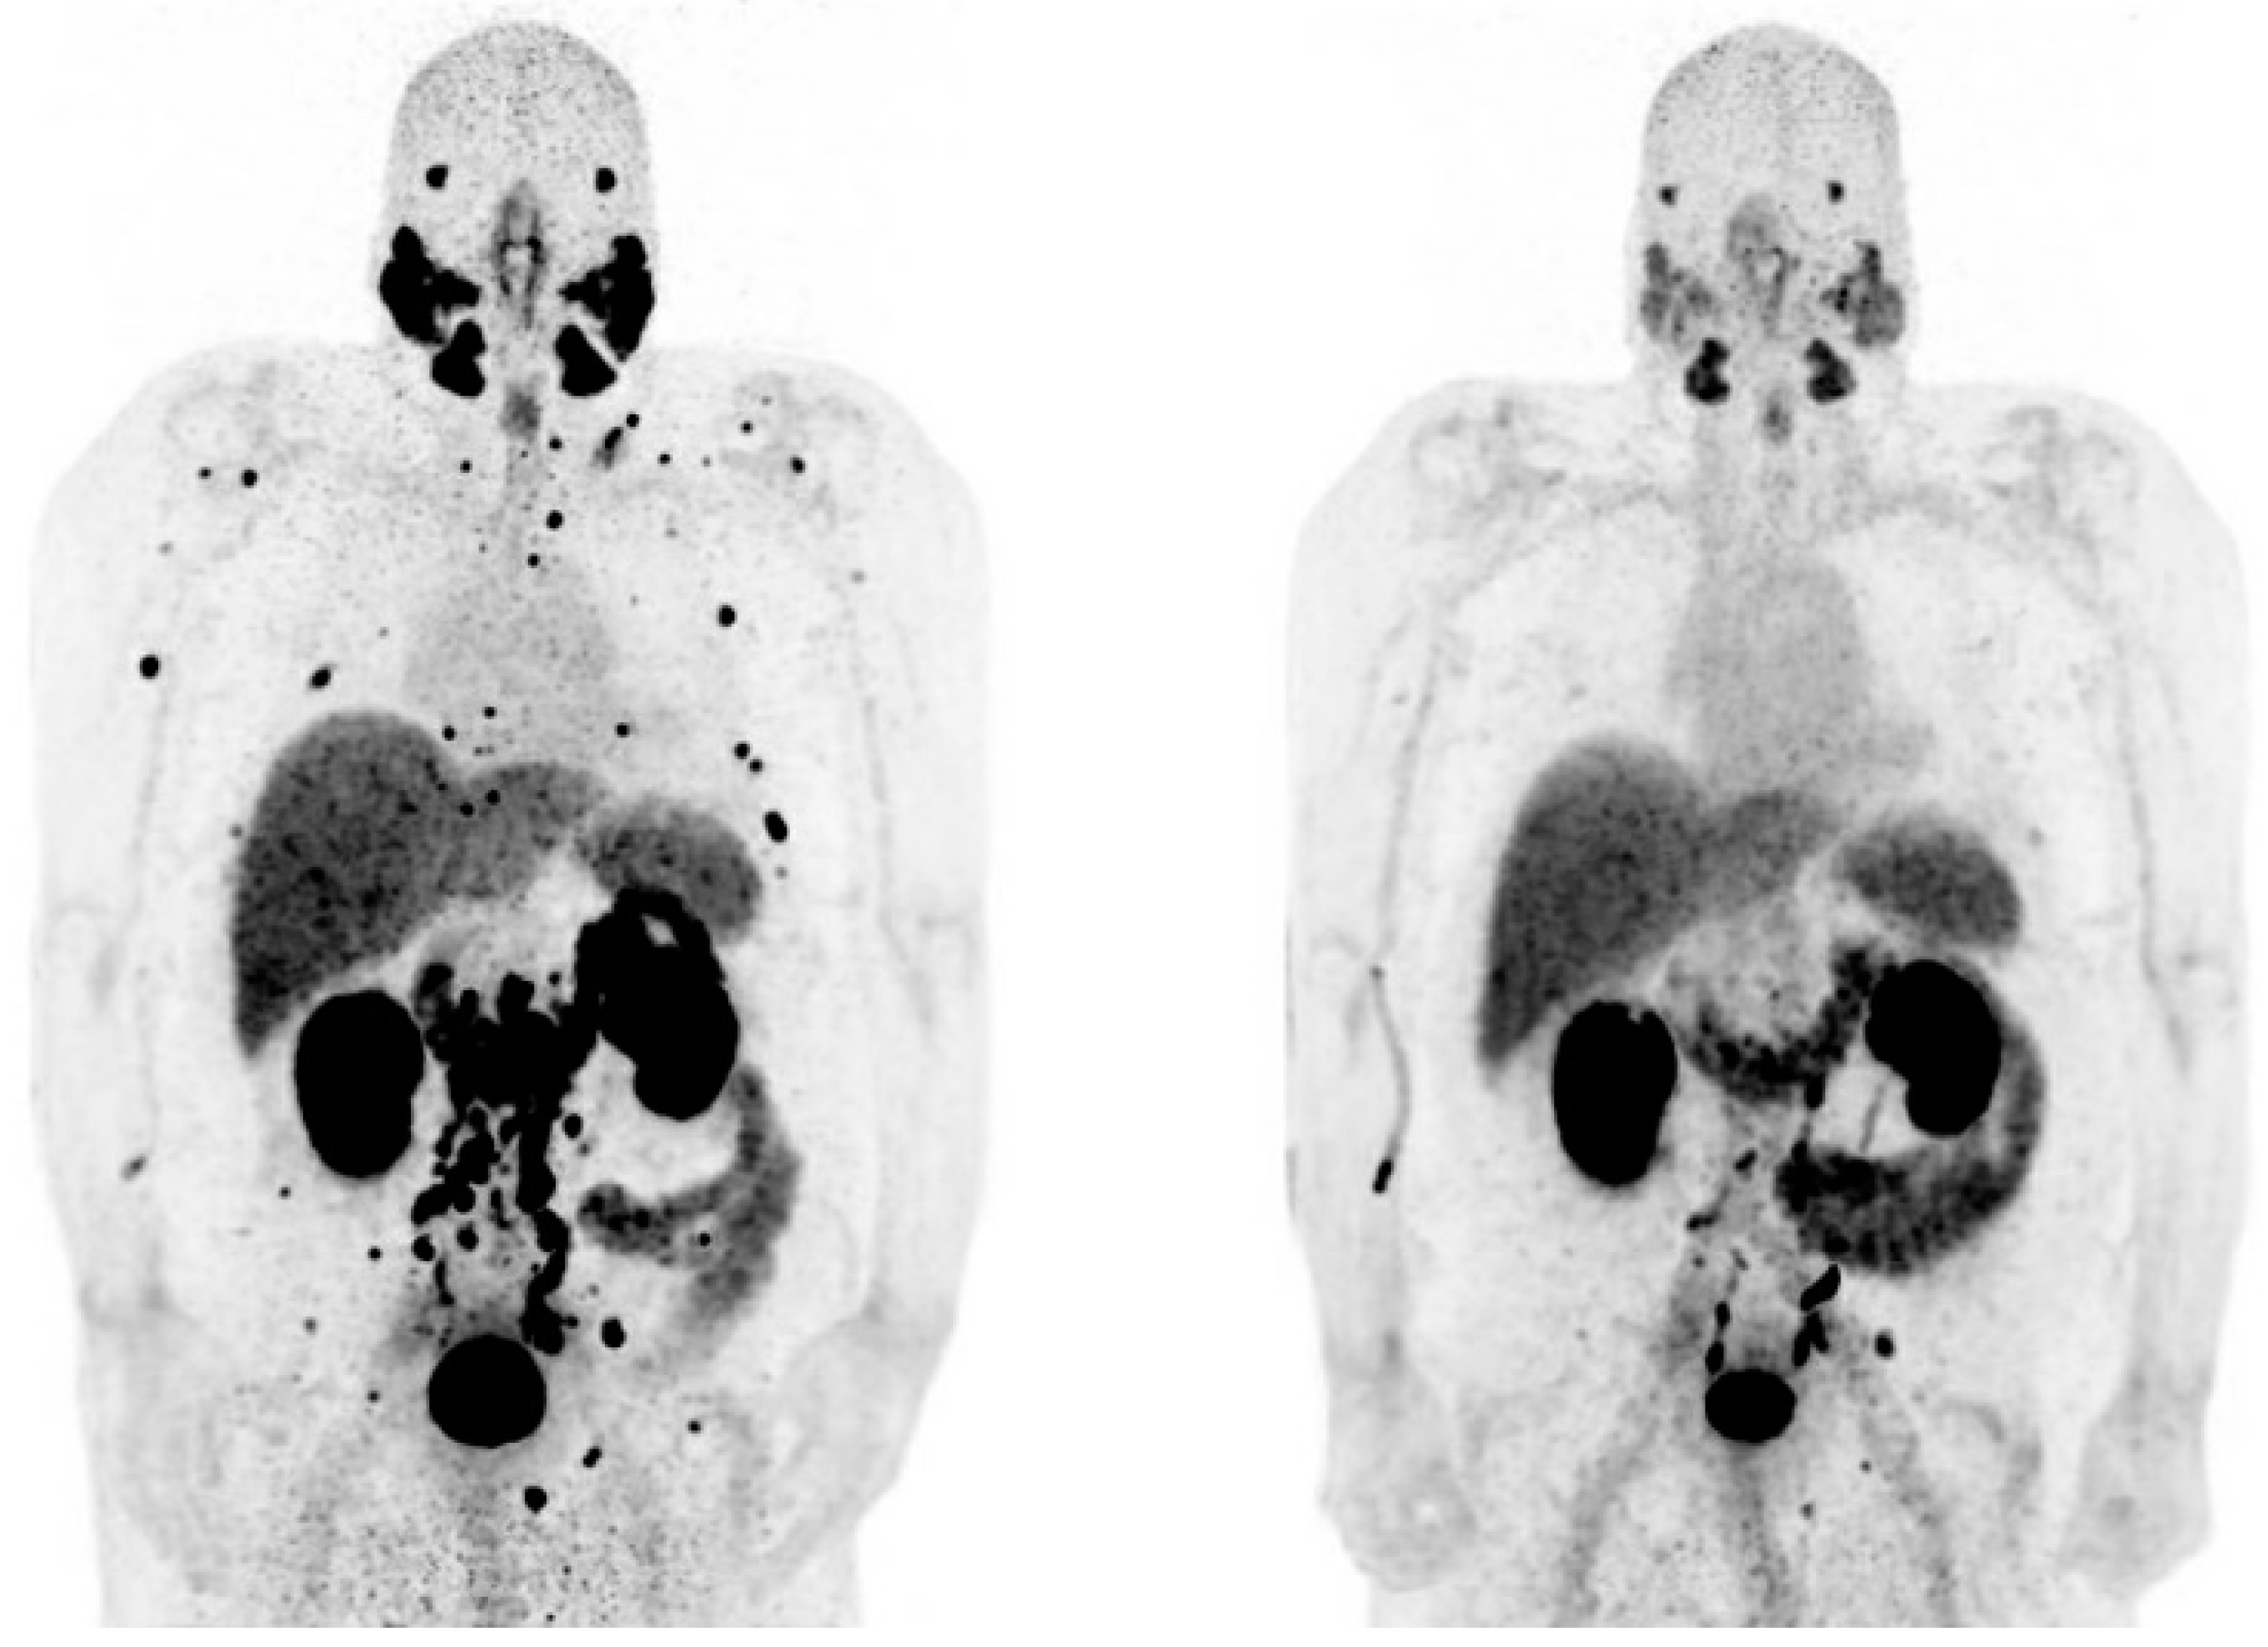

- Khreish, F.; Ebert, N.; Ries, M.; Maus, S.; Rosar, F.; Bohnenberger, H.; Stemler, T.; Saar, M.; Bartholoma, M.; Ezziddin, S. (225)Ac-PSMA-617/(177)Lu-PSMA-617 tandem therapy of metastatic castration-resistant prostate cancer: Pilot experience. Eur. J. Nucl. Med. Mol. Imaging 2020, 47, 721–728. [Google Scholar] [CrossRef]

- Rosar, F.; Hau, F.; Bartholoma, M.; Maus, S.; Stemler, T.; Linxweiler, J.; Ezziddin, S.; Khreish, F. Molecular imaging and biochemical response assessment after a single cycle of [(225)Ac]Ac-PSMA-617/[(177)Lu]Lu-PSMA-617 tandem therapy in mCRPC patients who have progressed on [(177)Lu]Lu-PSMA-617 monotherapy. Theranostics 2021, 11, 4050–4060. [Google Scholar] [CrossRef] [PubMed]